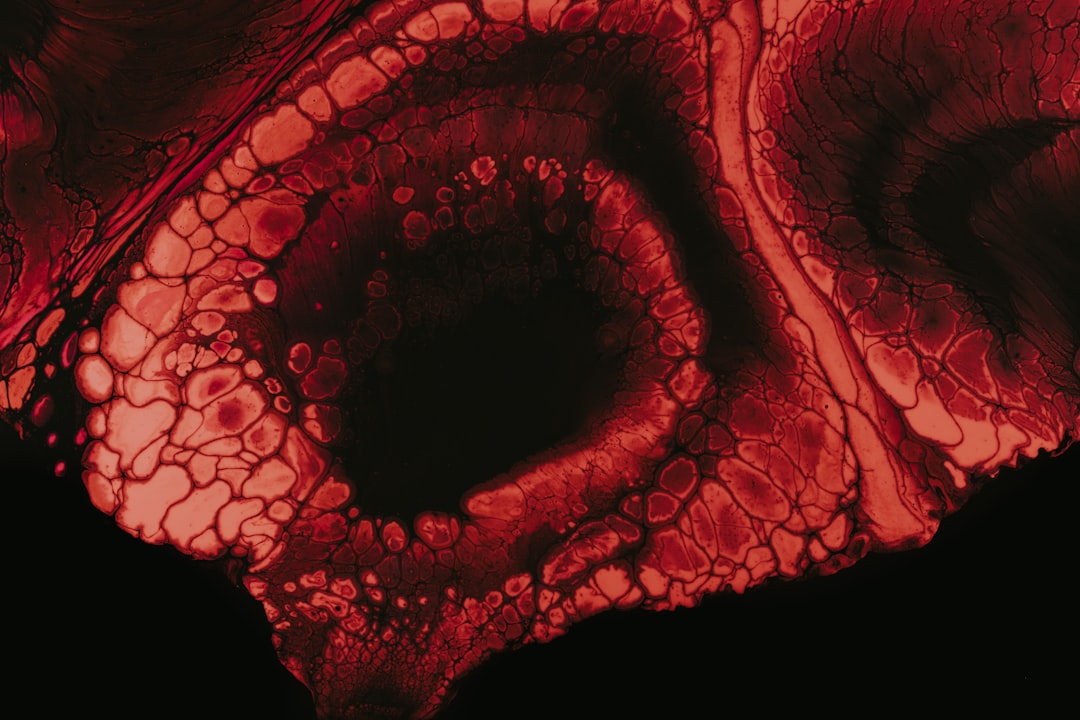

그렇다면 어떤 검사를 통해 이상을 감지할 수 있을까요? 정기적인 내시경 검사나 대변잠혈검사가 도움이 될 수 있습니다. 이러한 검사들은 수면 내시경 등으로 진행이 되어 상대적으로 편하게 받을 수 있습니다. 저도 처음에는 두려움이 있었지만, 검사가 끝난 후의 시원한 마음을 기억합니다. 매년 나의 건강을 체크하는 일, 이제는 필수라고 느껴집니다.